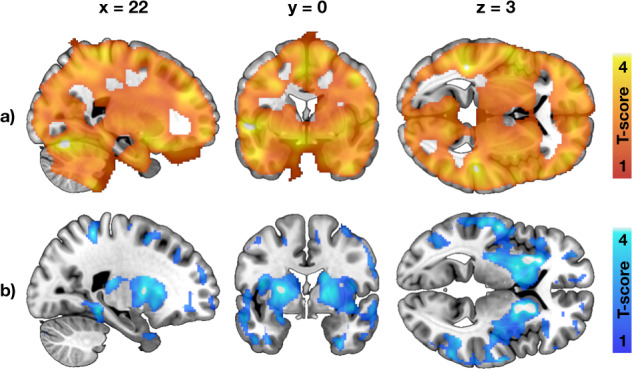

Increase in Family Risk was associated with globally increased in BGU (Fig. 3, all ROIs in Supplementary Fig. 2). BMI had a moderate positive association with BGU, while increased physical exercise associated with lower BGU (Fig. 3). Full volume visualization of the Family Risk associations is presented in Fig. 4.

μ-opioid receptor availability

Higher Family Risk was associated with lower BPND in frontotemporal cortex, insula and striatum (Figs. 3 and 4, all ROIs in Supplementary Fig. 2), while the effects of BMI and physical exercise markedly overlapped with zero.

First, since we studied only males, the conclusions may not be generalizable to females. Second, there was a small age-difference between the two risk groups. Age was however included in all analyses as a nuisance covariate. By study design, the BMI of HR group was higher than the BMI in LR group, since overweight in early adulthood is a predictive factor for future obesity [ref. 4]. However, compared to BMI, familial obesity risk had generally stronger and independent effects to the brain glucose uptake and neuroreceptor availability (Figs. 3 and 4). Also in healthy males, BMI in the range of 18–34 does not affect central MOR availability [ref. 37]. Third, we did not have the information about genetic profile of the subjects, and were therefore not able to directly assess the genetic obesity risk. Fourth, the information about physical exercise and parental risk factors were acquired by interview by licensed physician with a standardized medical history checkup, rather than by direct measurement. Finally, as a cross-sectional work this study cannot differentiate whether the detected cerebral alterations are the cause or the effect of increasing obesity risk or whether one receptor system’s alteration would serve as the primal cause for the detected changes in the other systems. In a single PET scan, it is also not possible to demonstrate the exact molecule-level mechanism for altered receptor availability [ref. 37]. Follow-up studies with assessment of eating behavior are needed to confirm the proposed effects of these brain signaling alterations to future weight gain.